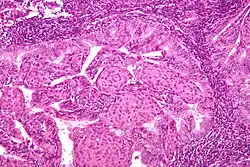

Pathology

- Epithelial tumors. For mesenchymal tumors, please see the uterine sarcomas page

- Papillary serous (1-5%)

- Complex papillary architecture, similar to papillary serous CA of ovary

- Presence of psammoma bodies

- Marked nuclear atypia

- Believed to transform from endometrial surface epithelium